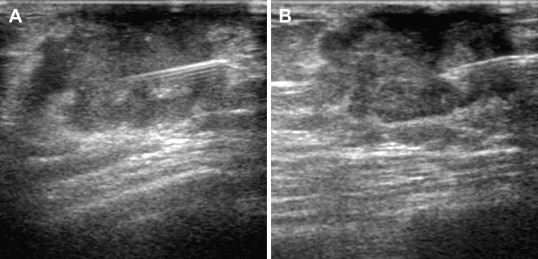

FNAC of a malignant breast tumor. Sonographic guidance allows real-time visualization of the position of the needle. The tip can be moved in different directions to obtain multiple samples within the tumor (A, B).

Figure 2.